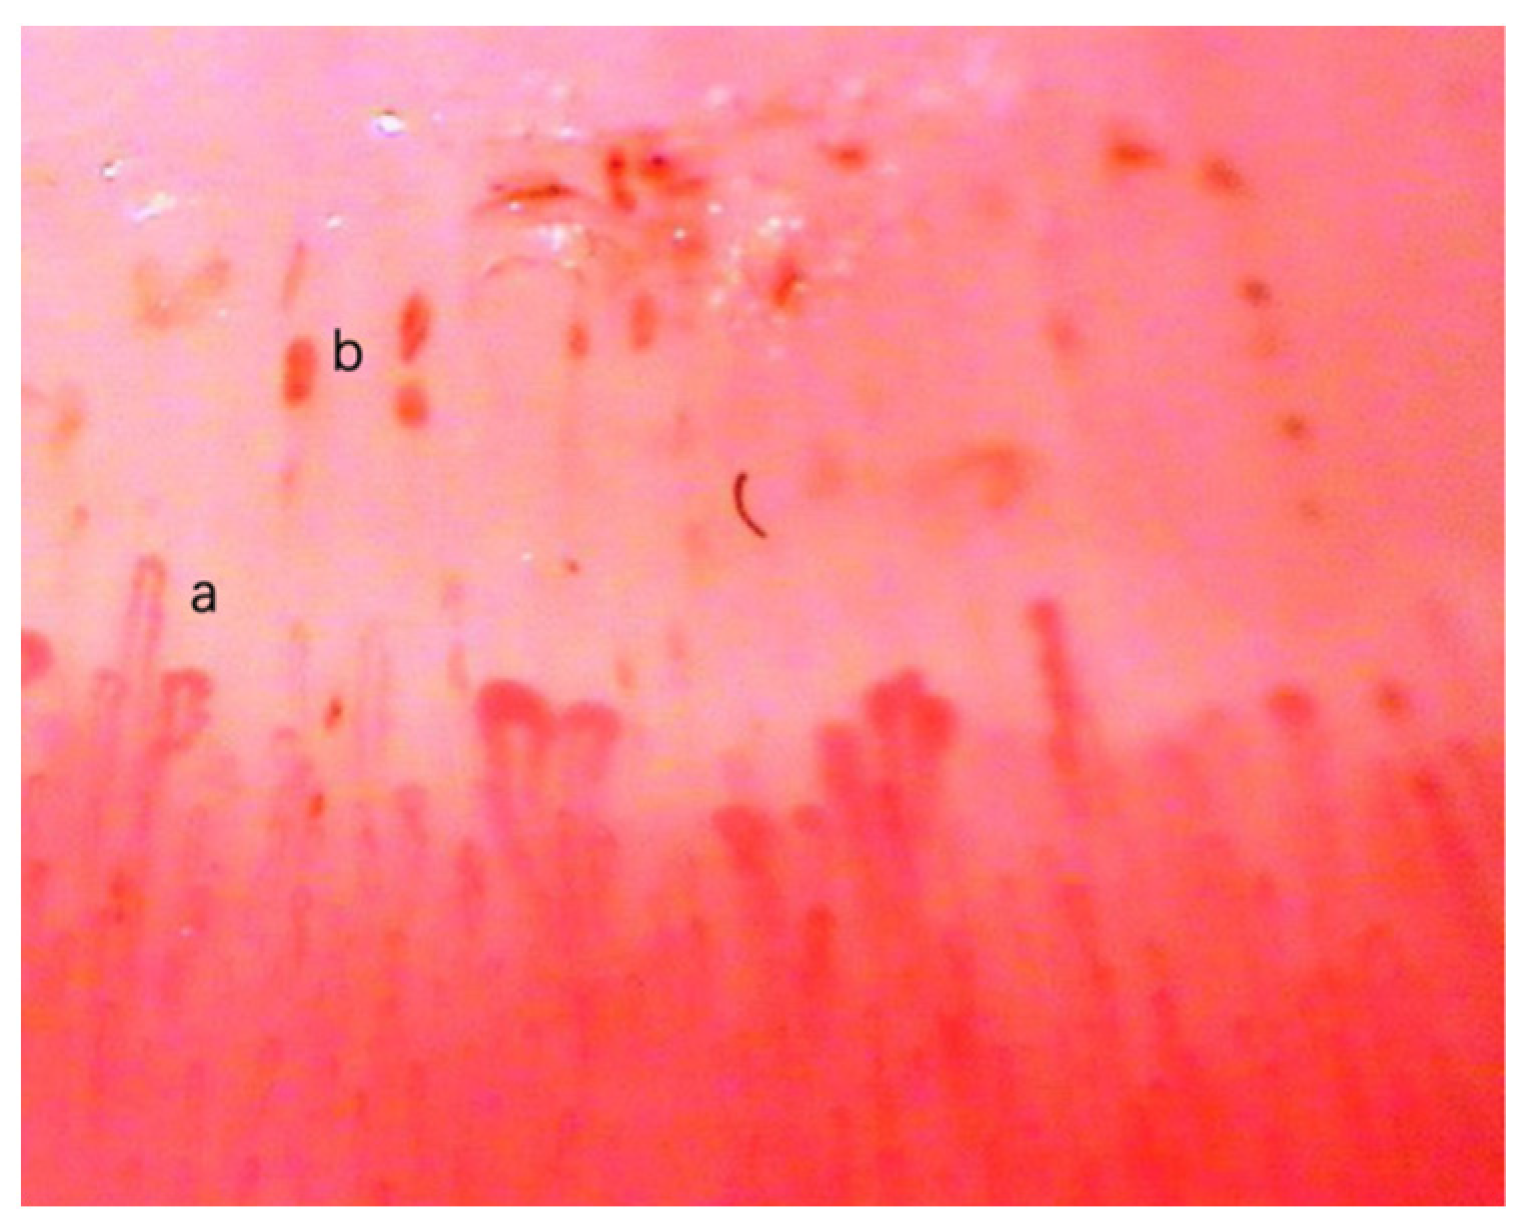

Nailfold microhemorrhages are defined as extravasation of red blood cells into the perivascular tissue as red or brown aggregations [5]. It is associated with the damage of the vessel wall and usually reflects the injury of capillaries. In particular, nail microhemorrhages may first manifest in nailfold microhemorrhages [6]. As illustrated in Figure 1, red cells leave the damaged capillaries and form punctuate hemorrhages and areas of the confluent hemorrhages [7].

Figure 1.

An example of nailfold microhemorrhages [7]. Nailfold capillaroscopy (a) and the nailfold microhemorrhages (b) in the figure.